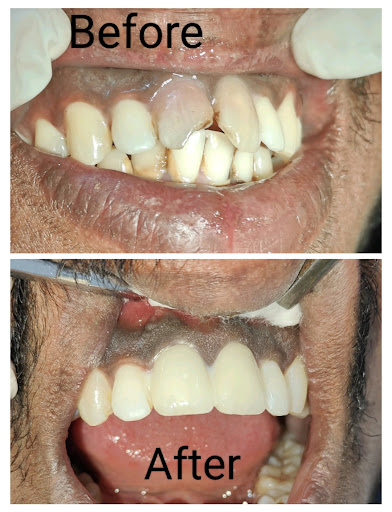

Gallery